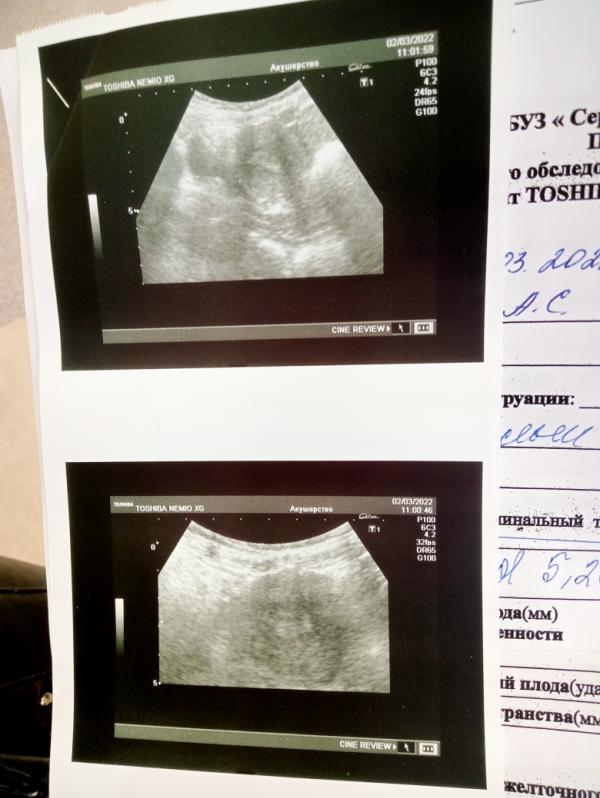

Вести с полей.... Сьездила в ЖК, итог- оформили в стационар, но находится буду дома... Посмотрела на кресле, сказала выделения скорее всего от гематомы... Сказала если коричневые это не так страшно (типо старая кровь), как красная.. Отправила на УЗИ, срок вообще поставили 2,5 недели😱😱😱, но врач сказала, что это нормально если такая разница т.к. УЗИ по животу было... типо к 10нед. точно сравняется...Назначила мне все то что я пила это Дюфастон и Транексам, только дозировку Дюфастона больше (4 таб в день), когда выделения закончатся будешь 3таб принимать...В обшем будем сохранять мою бусинку дома❤️❤️❤️